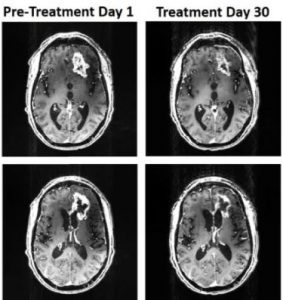

Un dispositivo que usa un campo magnético oscilante ha sido recientemente probado en un paciente de 53 años con un glioblastoma. El tumor se encogió en un 31% aunque el paciente falleció debido a un golpe en la cabeza no relacionado.

Consiste en sesiones de dos horas diarias hasta aumentarlas a seis horas, durante 36 días en los cuales el tumor se redujo 31%. Los familiares informaron a los investigadores una mejora en el habla y la función cognitiva.